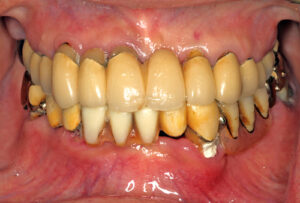

• 上下顎オールオン6症例

BEFORE AFTER 63歳男性/上顎6本・下顎6本 【治療内容】 全体的に歯が揺れてお食事がとりづらくなり、来院さ…